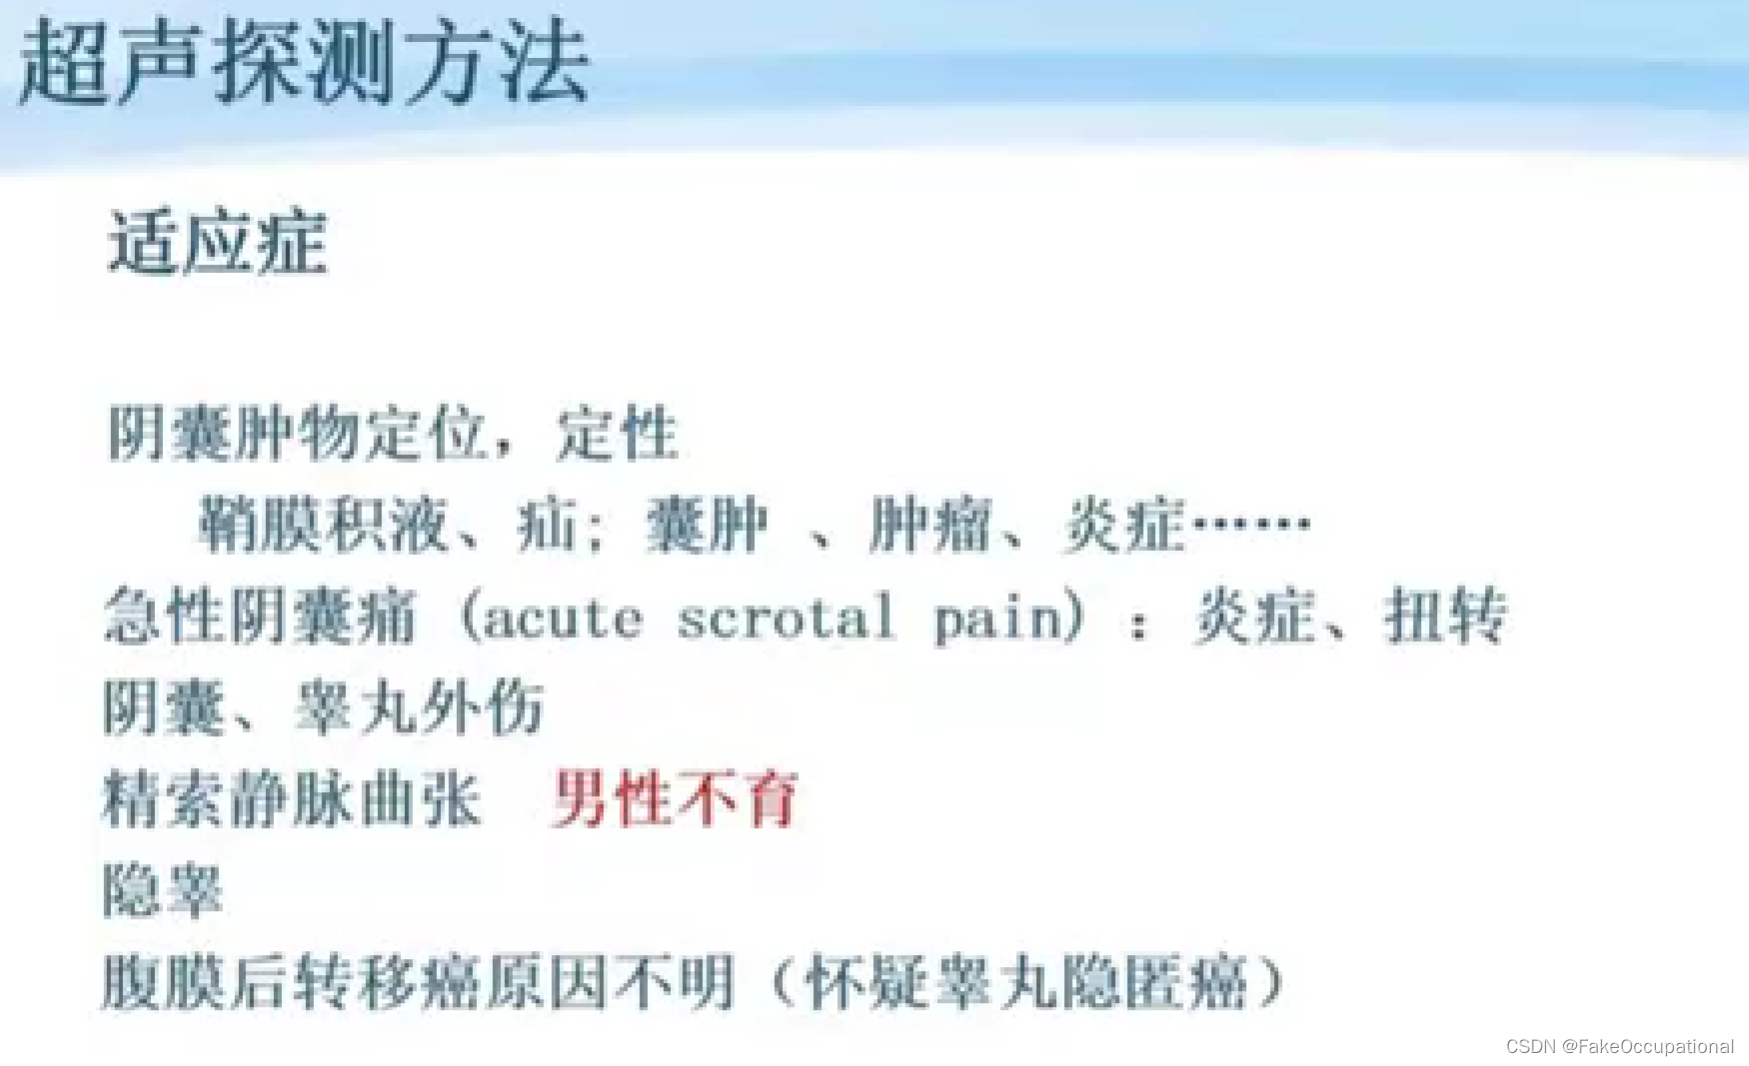

阴囊超声(和谐)